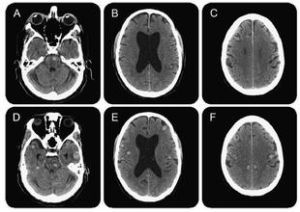

高白細胞急性白血病(HCL)通常是指臨床上將外周血白細胞計數≥100×109/L的急性白血病。因其發病急、病情進展迅速,早期死亡率高,是急診搶救範圍內的...